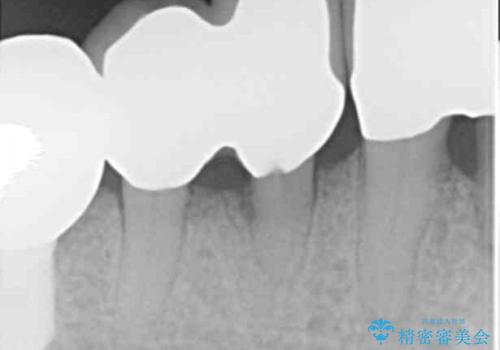

精査したところ、全顎的な重度の歯周病により右下の小臼歯(右下4)激しい動揺を認めました。

できるだけ自分の歯を残したいという患者様の強いご希望により、禁煙指導後再生療法(骨を増やす手術))を行いました。

再生療法から1年後リエントリー手術により骨の再生を確認し、骨外科処置(骨を平らにして歯周ポケットの根本的な改善を図る処置)を行ったのち、連結補綴を行いました。

再生療法と骨外科処置により、歯周ポケットは全周2mm以下に改善されました。

歯周病治療と連結補綴により歯の動揺がなくなり、「なんでも食べられます!」と喜んで下さいました。